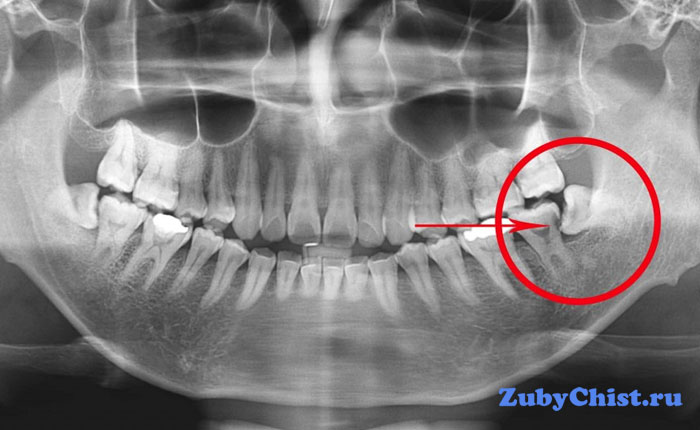

- Аномальный наклон. По-другому именуется дистопией. Слишком острый градус наклона, мешающий росту других зубов, останавливает развитие нового моляра. Наткнувшись на препятствие, восьмерка прекращается расти. Но при этом, если моляр отклонился назад, то давление на область тройничного нерва вызовет болезненные ощущения.

Аномальный наклон